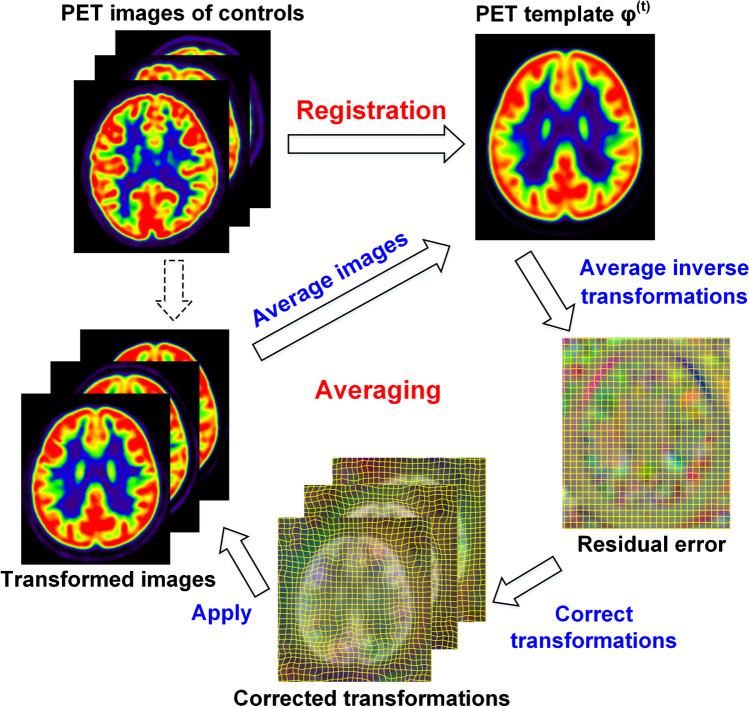

Fig. 1.

Flowchart of iterative registration-averaging optimization. This optimization approach iterated between registration and averaging steps to create unbiased brain template

The iterative optimization procedure satisfied the two constraints simultaneously by repeating registration and averaging steps. At iteration t, the registration step spatially normalized all PET images to an approximated template image . The averaging steps included:

Average non-rigid components in the inverse transformation of as residual error . The residual error characterizes unwanted deformations of spatial normalization.

Correct transformations by composition with residual error: . In this way, unwanted deformations can be removed to satisfy the morphological constraint.

Transform PET images by corrected transformations, and average transformed images as the approximated template image in the next iteration: . This step satisfies the metabolic constraint.

The development procedure stopped when the mean squared difference between two consecutive template images was less than convergence level (0.0001). In concern of computing speed, a coarse-to-fine creation approach was adopted by using affine registration, 2-mm symmetric diffeomorphic normalization (SyN) nonlinear registration and 1-mm SyN sequentially [15]. To correct transformations, matrix multiplication was used for affine registration, and field composition for SyN registration: , where and were two deformation fields, denoted voxel coordinate. After development, brain regions of PAPT were partitioned according to the Desikan-Killiany atlas [16], which could provide anatomical information for future studies (Supplementary Materials S1). The template development process was implemented by an in-house software based on Insight Toolkits library (http://www.itk.org/).